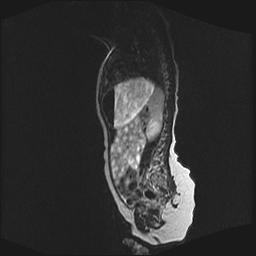

四个月的女婴,ct示脊膜膨出.

脂肪脊髓脊膜膨出

脊柱裂、脊膜膨出